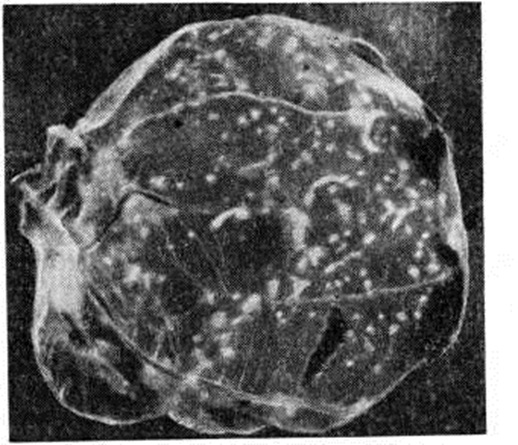

Вирус выделяют заражением 11 — 12-дневных куриных эмбрионов (на хорион-аллантоисную оболочку), белых мышей (в мозг), кроликов (на роговицу), а также заражением первично-трипсинизированных и перевиваемых линий клеточных культур. На хорион-аллантоисной оболочке куриных эмбрионов формируются бляшки (рисунок) диаметром 1 — 2 миллиметров, у кроликов на роговице развивается кератит, у белых мышей — энцефалит, в тканевых культурах — деструкция клеток (так называемый цитопатический эффект).

Рис

Хорион-аллантоисная оболочка куриного эмбриона, заражённого вирусом простого герпеса: видны бляшки (белые пятна).